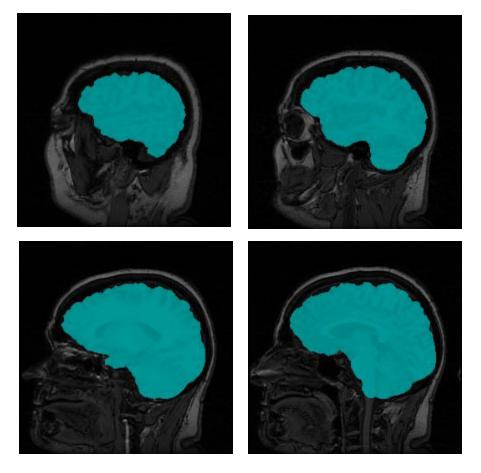

The end result is a ternary 3D image whose voxels are 0 for background, 1 for surface, and 2 for interior. The distinction between the surface and interior voxels allows an application to color the surface voxels in image slices to see how accurate the segmentation is. Figure 5 shows a few slices of the original MRI with the brain voxels colored.

Figure 5. MRI slices with colored brain voxels.